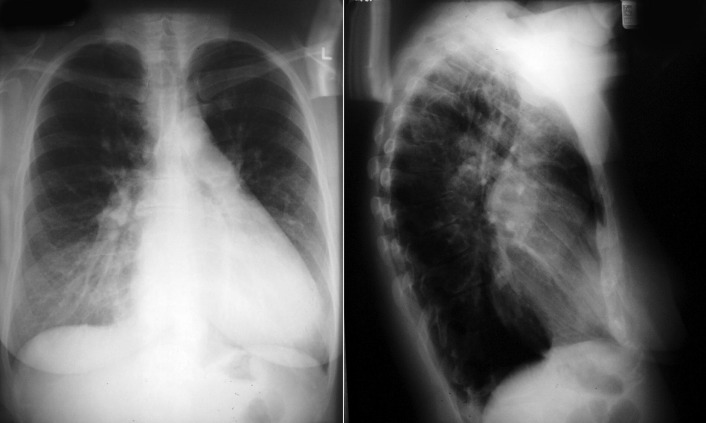

A patent foramen ovale is present in 25% to 30% of the adult population ( Figs. 18-1 to 18-4 ). Any magnitude of shunting across it in normal circumstances is undetectable radiographically. Percutaneous patent foramen ovale closure devices are fairly commonly inserted and are radiographically evident.